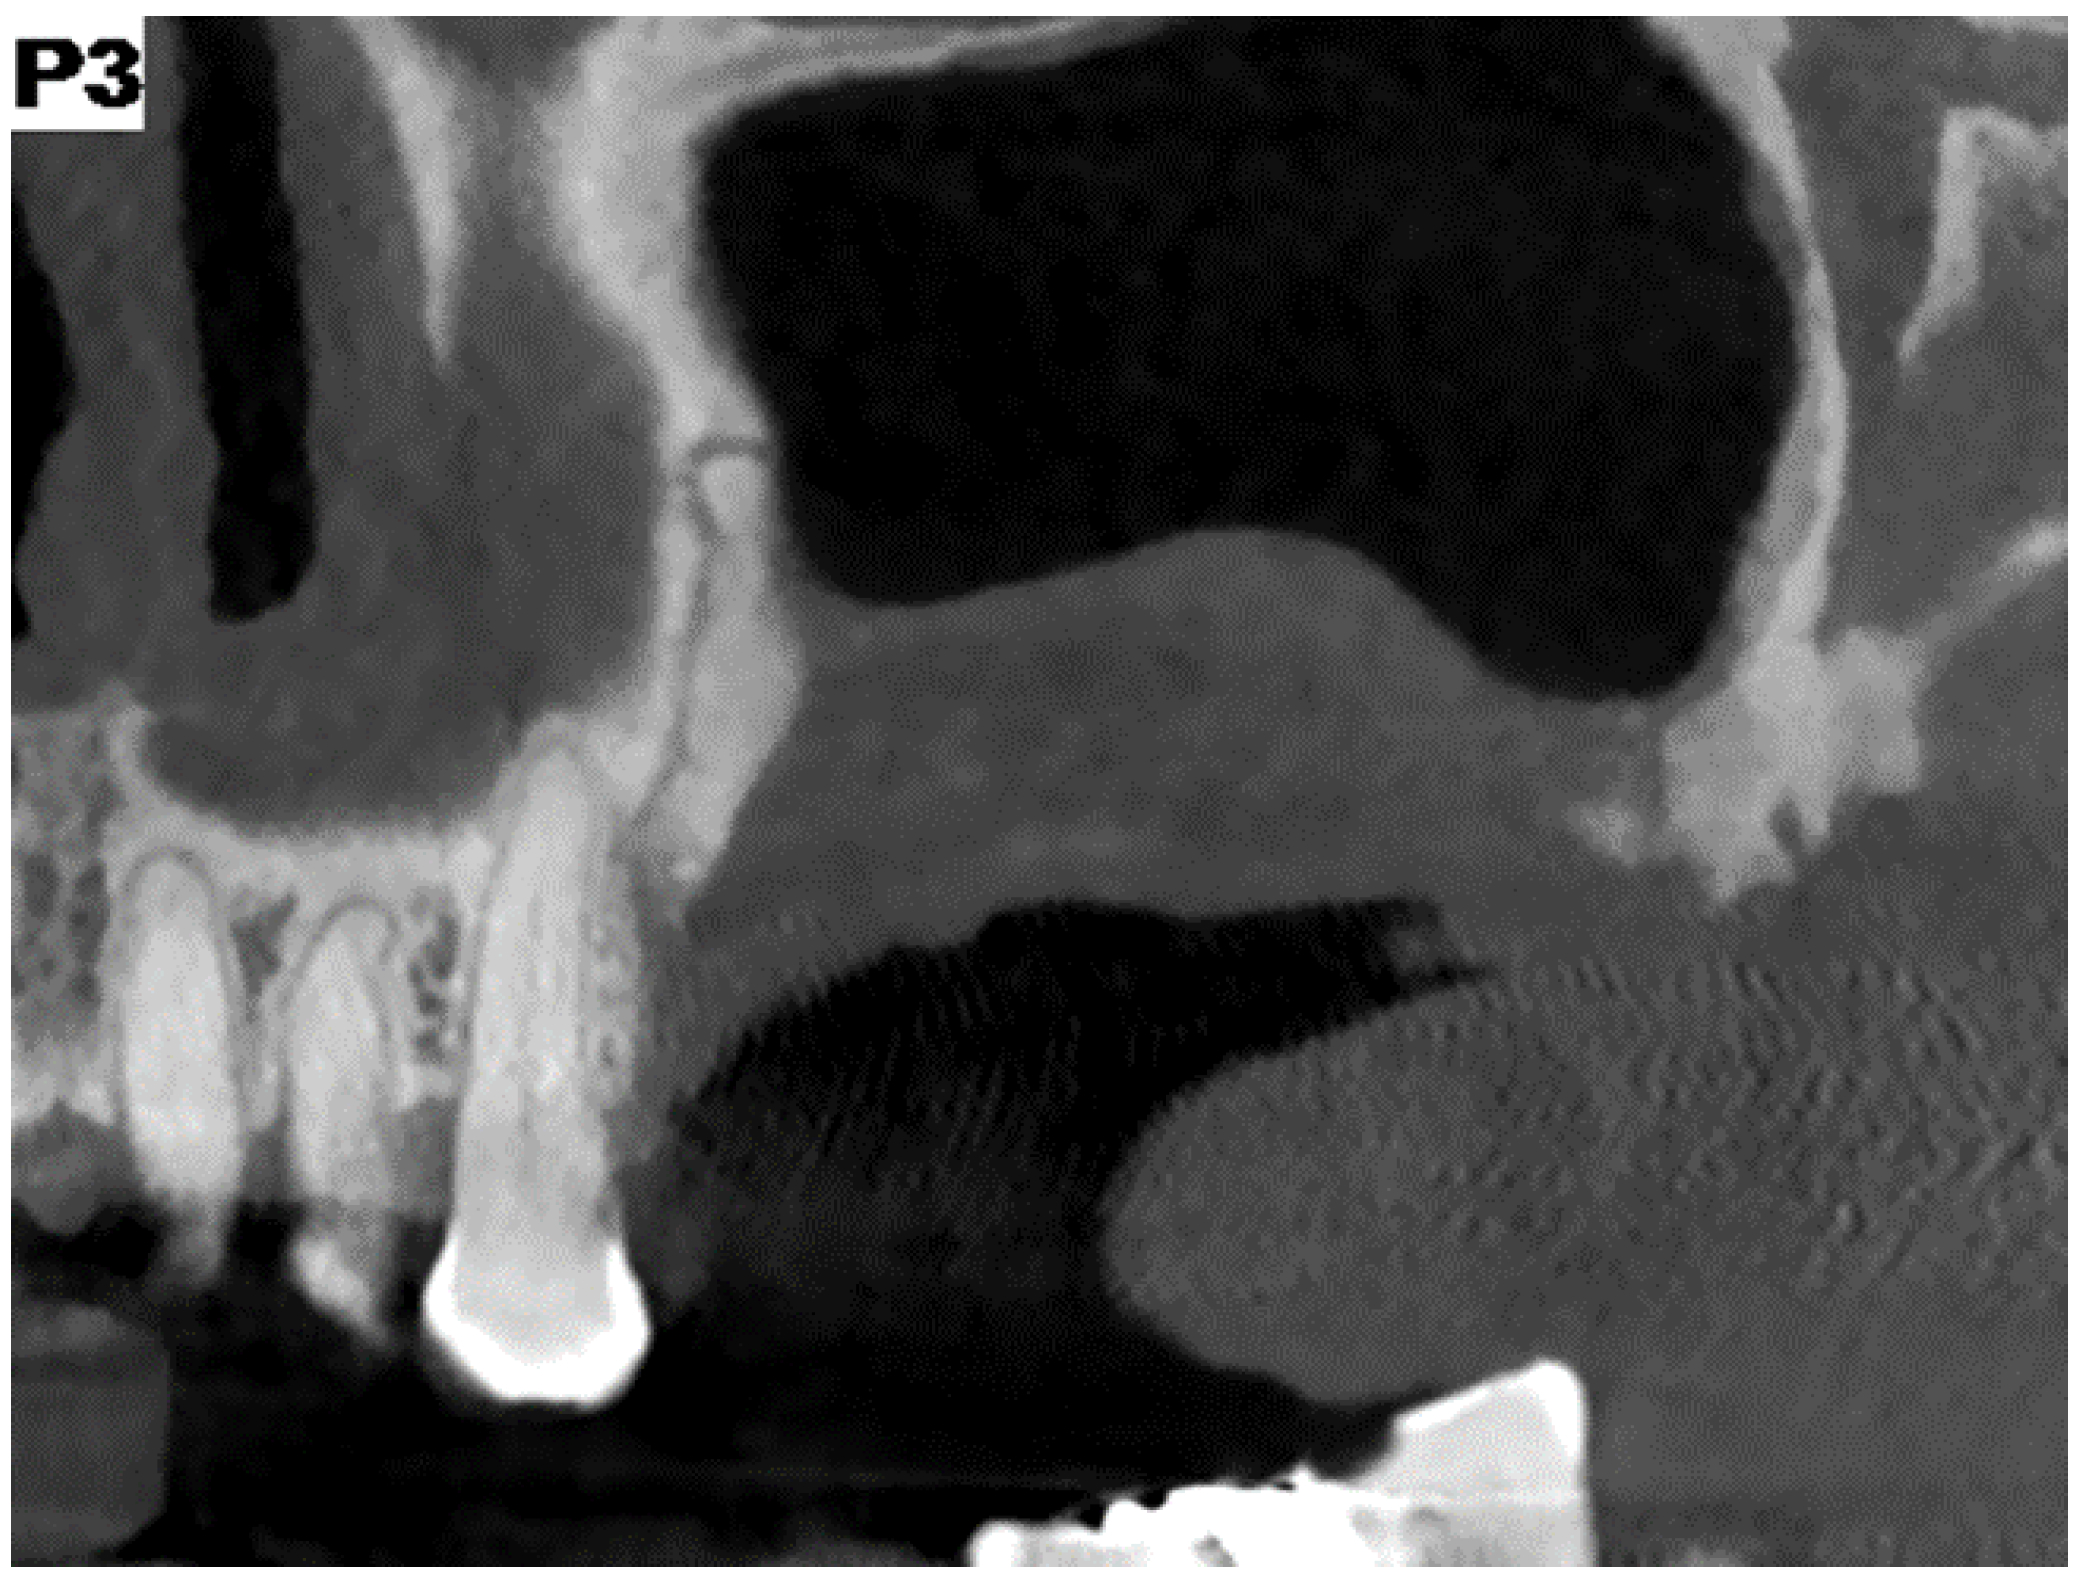

Figure 1. Preoperative CBCT showing a spontaneous bisphosphonates related osteonecrosis of the (upper) jaw in a patient with multiple myeloma treated with zoledronic acid (4 mg × 18 doses).